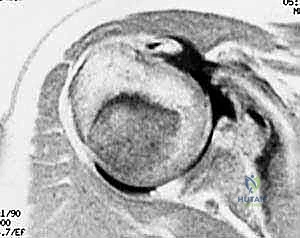

| الموجات فوق الصوتية (Ultrasound) | فحص ديناميكي للأوتار أثناء حركة الكتف، رخيصة وسريعة. | كفحص مبدئي لتقييم الكفة المدورة ووتر ذات الرأسين. | متوسطة إلى جيدة، تعتمد على مهارة الفاحص. |

| الرنين المغناطيسي (MRI) | المعيار الذهبي. يظهر تفاصيل الأنسجة الرخوة، حجم التمزق، وتراجع العضلة. | لتأكيد التشخيص والتخطيط الدقيق للعملية الجراحية. | دقة ممتازة وتفاصيل ثلاثية الأبعاد. |

2. تنظير المفصل الاستكشافي الدقيق (Diagnostic Arthroscopy)

يقوم الدكتور هطيف بعمل شقوق صغيرة جداً (ثقوب بحجم ثقب المفتاح) حول الكتف. يتم إدخال كاميرا عالية الدقة (4K) وأدوات جراحية دقيقة. يتم ضخ سائل معقم داخل المفصل لتوسيعه وتوفير رؤية واضحة. يبدأ الجراح بفحص المفصل بالكامل من الداخل لتقييم حجم التمزق، حالة الغضاريف، ووضع وتر العضلة ذات الرأسين.